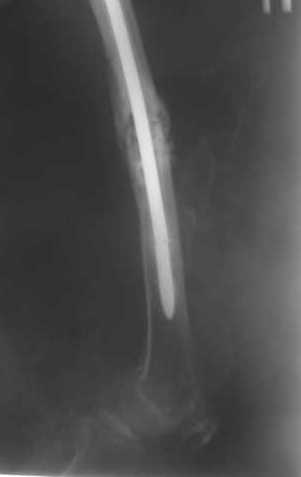

> Очень было бы любопытно посмотреть поэтапные Р-снимки с ЭОПа (хотя

В приложении пример, как их использовали после остеотомии бедра по поводу сросшегося с вальгусом перелома, чтобы не дать гвоздю уйти во внутренний мыщелок.

Да, действительно красивый клинический пример: виден вальгус до операции и последующая коррекция углового смещения на "полярах". Я так понимаю, что в вашей клинике есть возможность использовать различные фиксаторы. Почему не использовали DFN? Спицы какие используете? Киршнера или Илизаровские? С виду очень тонкие...